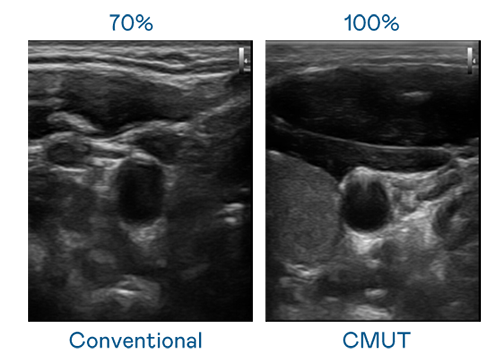

CMUT 技术是一种用电容式微机电元件来产生超音波讯号的技术。与传统 PZT 压电式技术相比,CMUT 频宽增加 30%,更宽频的超音波讯号让影像解析度大幅提升,是实现高影像品质医疗超音波扫描、促进精准医疗发展的关键技术。

超音波影像的解析度高低,首先取决于探头能发出的讯号频宽。太阳成集团tyc151cc CMUT 可提供高清晰的超音波讯号,提供高频宽、高灵敏度、影像纹理细节更高的超音波影像,协助医护人员缩短影像判读时间及利用精准的医疗影像进行诊断。